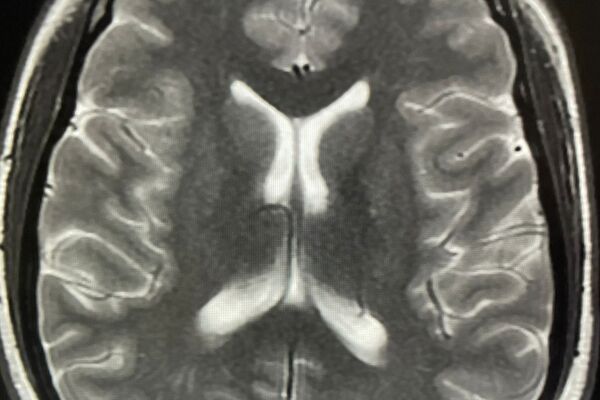

Das Aufgabengebiet der Neuroradiologie umfasst die Diagnostik von Erkrankungen und Veränderungen des Zentralen Nervensystems (ZNS), d.h. von Gehirn und Rückenmark. Das Gehirn ist ein äußerst komplexes Organ des menschlichen Körpers, so dass die Neuroradiologie eine mehrjährige Spezialisierung im Fachgebiet Radiologie erfordert, die vergleichbar mit der Kardiologie im Fachgebiet der Inneren Medizin oder der Gehirnchirurgie im Fachbereich der Chirurgie ist.

Diagnostik und Befundung in der Radiologie sind im Verlauf der letzten Jahre immer komplexer und anspruchsvoller geworden. Mit der spezialisierten Neuroradiologischen Diagnostik bieten wir Ihnen in unserer Praxis eine besondere Expertise in der Auswertung Ihrer Untersuchungen an.

Beispiele für spezielle Neuroradiologische Fragestellungen:

1. Diagnose und Verlaufskontrollen entzündlicher Erkrankungen des ZNS (insbesondere Kontrolle der Therapie bei Multipler Sklerose)

2. Diagnose und Verlaufskontrollen von Kopf- und Halstumoren (Therapiekontrolle, frühes Erkennen von Tumorrezidiven oder Tumorwachstum)

3. Spezielle Demenzdiagnostik (Ausschluss anderer Ursachen, Einordung der Demenzart)

4. Abklärung von Kopfschmerzen, Schwindel, Tinnitus, Hör- und Sehstörungen usw.

5. Ursachenforschung bei Lähmung der Gesichtsmuskeln (Facialisparese), Schmerzzuständen der Gesichtshaut (Trigeminusneuralgie) oder Schädigungen der übrigen Hirnnerven

6. Rückenschmerzen mit Ausstrahlung in Arme oder Beine (Bandscheibenvorfall, knöcherne Einengungen durch Arthrose)